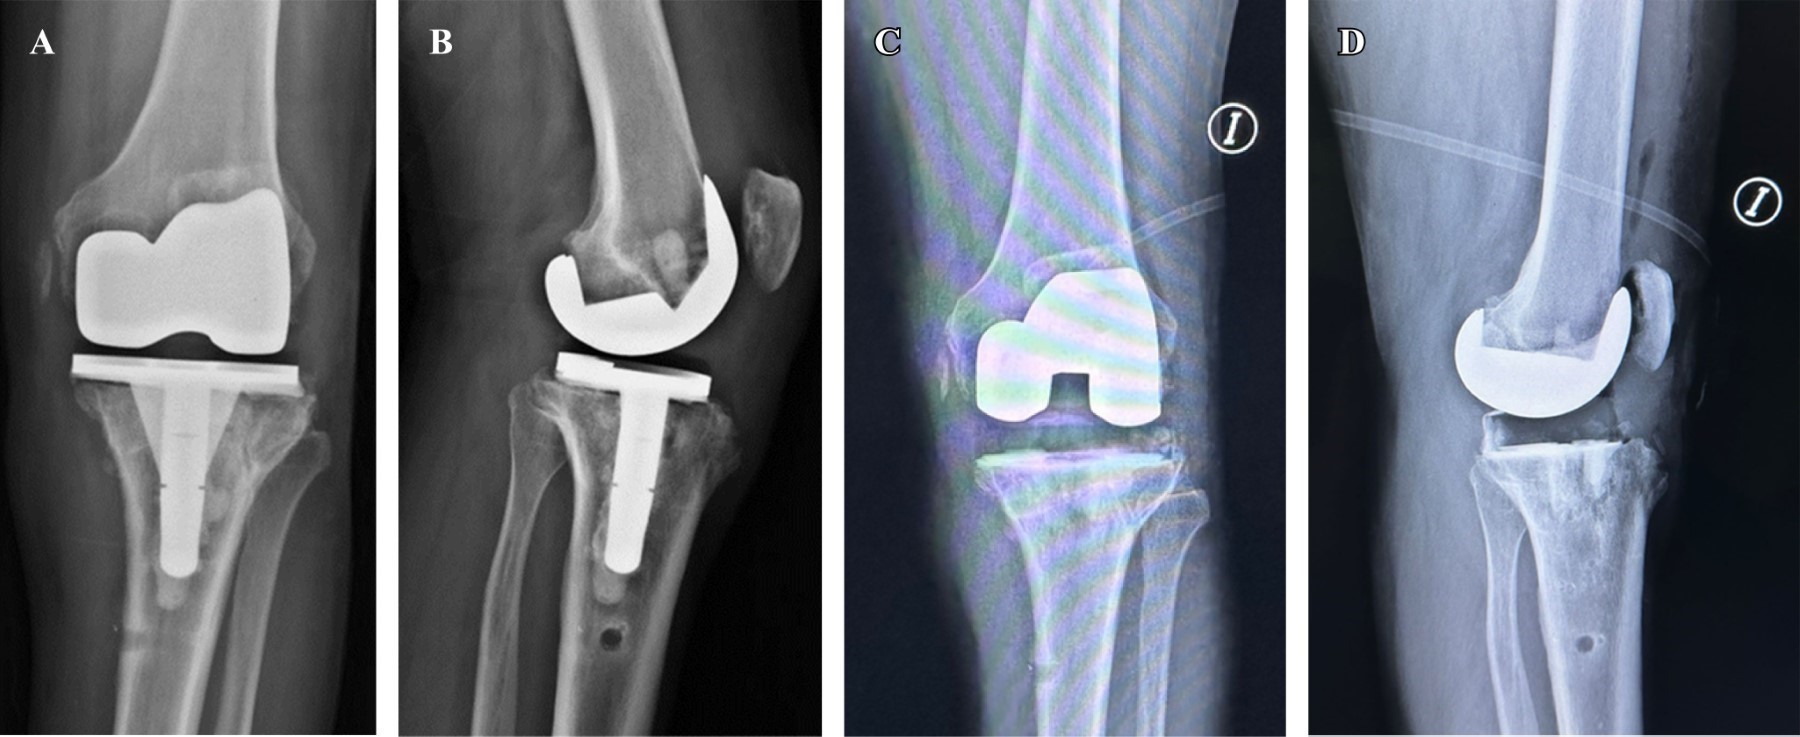

Figure 1

Figure 2

Figure 3

Figure 4

Figure 5

Figure 6

Figure 7